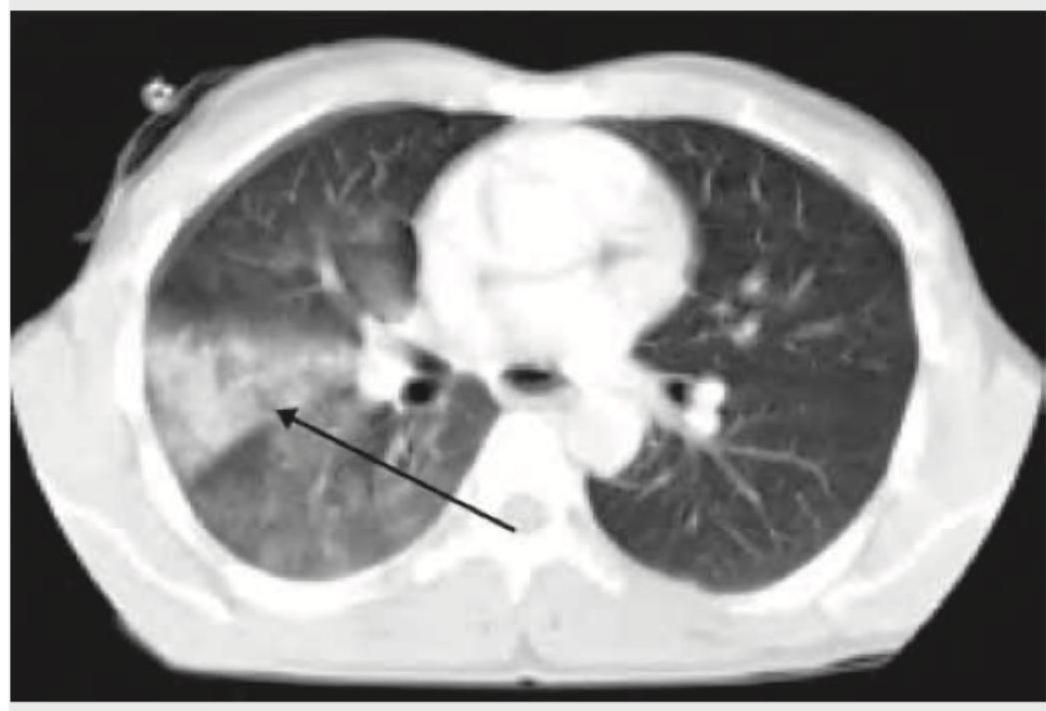

A cement slab fell on the chest of a 20-year-old construction worker. The arrow in the given CT chest points to:

Question 11: A cement slab fell on the chest of a 20-year-old construction worker. The arrow in the given CT chest points to:

- A. Lung contusion (Correct Answer)

Explanation: ***Lung contusion*** - The image shows an area of **ground-glass opacity** and **consolidation** within the lung parenchyma, consistent with **hemorrhage and edema** caused by blunt force trauma. - This finding, combined with the history of the cement slab falling on the chest, is highly suggestive of a **lung contusion**. *ARDS* - **ARDS** (Acute Respiratory Distress Syndrome) is a clinical syndrome characterized by widespread **inflammatory lung injury**, typically presenting as bilateral infiltrates on imaging. - While it can manifest with similar CT findings, ARDS is a **diagnosis of exclusion** and requires specific clinical criteria (e.g., severe hypoxemia, exclusion of cardiac failure) not provided in the question. *Diaphragmatic rupture* - A **diaphragmatic rupture** involves a tear in the diaphragm, which would appear on CT as a discontinuity of the diaphragm or **herniation of abdominal contents** into the thoracic cavity. - The image does not show any signs of diaphragmatic discontinuity or organ herniation. *Pneumothorax* - A **pneumothorax** is the presence of air in the pleural space, which would be visible as a collection of **dark air outside the lung parenchyma**, often with a visible pleural line and collapse of the lung. - The CT scan shows parenchymal changes rather than a collection of air in the pleural space.